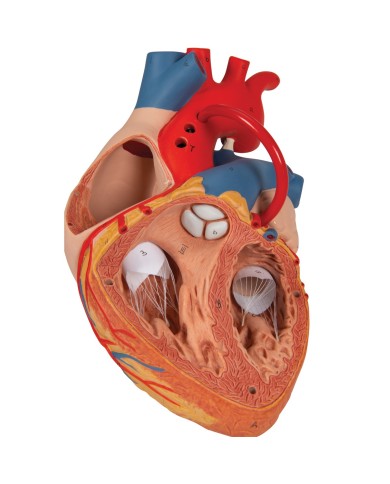

Modello di cuore di alta qualità scomponibile in 5 parti

Modello di cuore di alta qualità scomponibile in 5 parti

La parete anteriore del cuore è staccabile per poter vedere i ventricoli.

Realizzato in stampa 3D ad elevatissima risoluzione a colori.